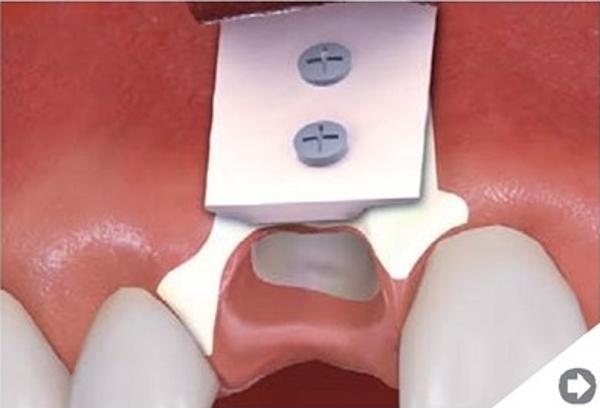

Sterowana regeneracja kości. Poszerzenie wyrostka zębodołowego żuchwy.